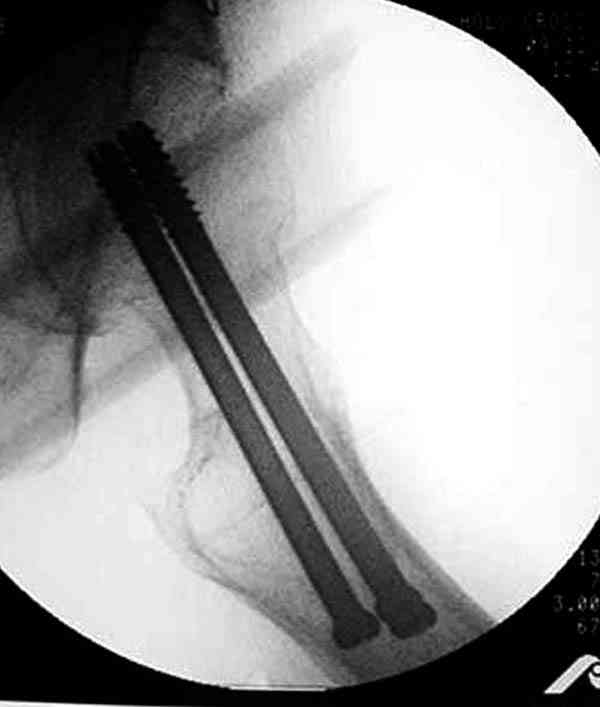

Здесь случай перелома из-за ослабления латерального кортекса через 3 недели после операции на шейке. Шурупы были установлены под большим углом, слабый латеральный кортекс не выдержал нагрузку.